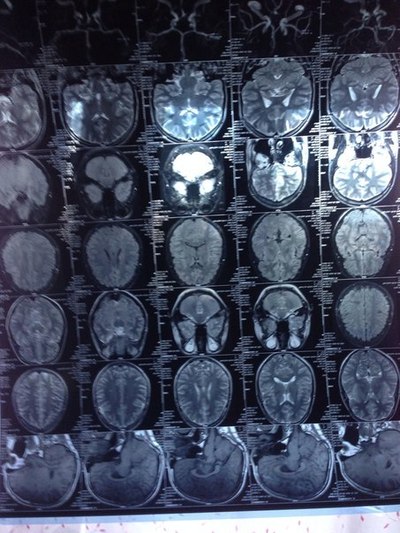

При МРТ с тебя с наушниками даже к процедурному кабинету не подпустят.

Может все таки ЭЭГ?